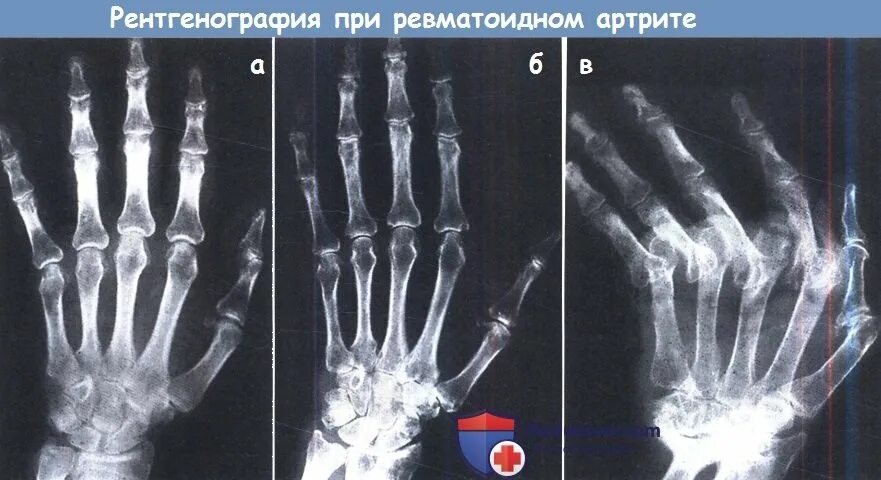

Артрит суставов стадии